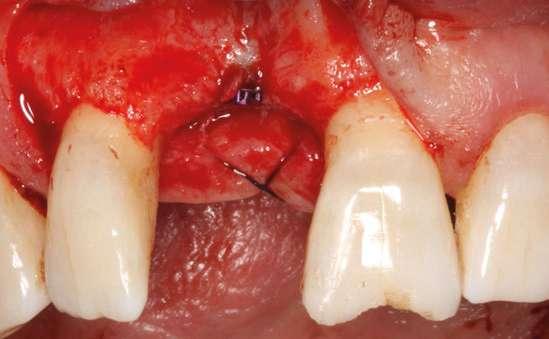

Colocamos el implante generándose una ligera expansión vestibular, como mostramos en las imágenes intraoperatorias, para posteriormente ser sobrecorregido con hueso autólogo obtenido del fresado, embebido en PRGF-endoret y lograr una mayor anchura vestíbulo-lingual en la zona de colocación del im-

plante, clave para lograr una mejor estética y además un mantenimiento de los tejidos periimplantarios a largo plazo. En la fase quirúrgica colocamos además el transepitelial unitario para la realización de la carga inmediata y la colcación de un provisional atornillado horas después de la cirugía (figuras 7-14).

Figuras 7 y 8. Perforación inicial y colocación del implante expandiendo la zona vestibular.

Figuras 9 y 10. Visión vestibular tras la inserción del implante y colocación del transepitelial unitario para comenzar la carga inmediata.

Figuras 11 y 12. Sobre-corrección vestibular y cierre primario de los tejidos con un monofilamento no reabsorbible alrededor de la tapa de protección del transepitelial.